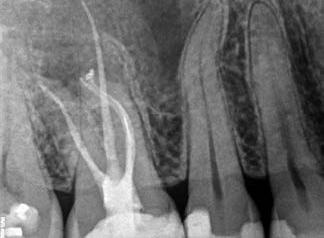

1. a-n. ábrák: Preoperatív CBCT-felvétel a bal alsó 6-os (3.6) fogról. Az axialis (a), coronalis (b) és sagittalis (c) nézeteken a mezialis és distalis gyökerek apicalis harmada körül sugáráteresztő zóna és ép buccalis corticalis csont látható. Egy olyan sablont terveztünk, amely jelezte a csontablak határait az apicalis terület pontos elérése érdekében (d). A mikrosebészeti bevatkozás során a sablont a helyére illesztettük (e), a csontablak határait megjelöltük (f) egy Piezotome CUBE LED kézi-darabba fogott fűrésszel, majd kivágtuk és eltávolítottuk (g és h) az apicalis területhez történő hozzáférés, illetve a mezialis és distalis gyökerek rezekciójának, retrográd preparációjának és retrográd gyökértömésének elvégzése érdekében (i). Végezetül a csontablakot visszaillesztettük és kollagén szivaccsal stabilizáltuk (j). A műtét után közvetlenül készített röntgenfelvétel a 3.6-os fogról (k). A kétéves kontroll során készített CBCT-felvétel: axialis (l), coronalis (m) és sagittalis (n) nézetek.

Egy 63 éves páciens korábban már kezelt bal alsó első nagyőrlőfogából (3.6) eredő mérsékelt fájdalom miatt kereste fel rendelőnket. A kórtörténetében panasza szempontjából releváns információ nem szerepelt. Az elkészült CBCT-felvételen a korábbi kezelések során észre nem vett, jelenleg feltáratlan meziobuccalis csatornát, valamint a mezialis és distalis gyökerek körül kialakult periapicalis elváltozást, és ezt a léziót borító intakt buccalis corticalis csontlemezt láttunk.

Klinikai vizsgálat során vertikális kopogtatási érzékenységet jelzett. A fog körül mérhető szondázási mélység és a fogmobilitás fiziológiás volt. A CBCT-felvételen nem észleltünk a csontos regeneráció megindulására utaló jeleket (1. a–c. ábrák). A korábban gyökérkezelt, gyökértömött és revideált 3.6-os fog esetében az alábbi diagnózis került felállításra: periodontitis periapicalis symptomatica. A panaszokat okozó fog további ellátása során navigált endodonciai mikrosebészetet kívántunk alkalmazni. Az alsó állcsontról intraorális szkent (TRIOS, 3Shape) készítettünk, és a felszíni topográfiát tartalmazó STL fájlt, valamint a CBCT-felvétel készítése során nyert DICOM fájlokat a Blue Sky Bio szoftver segítségével egyesítettük. A sebészi sablon megtervezésére az így kapott háromdimenziós képet használtuk. A sablon kialakítása során arra törekedtünk, hogy a sablon egyértelműen meghatározza a gyökércsúcsi terület eléréséhez szükséges csontablak határait (1. d. ábra)